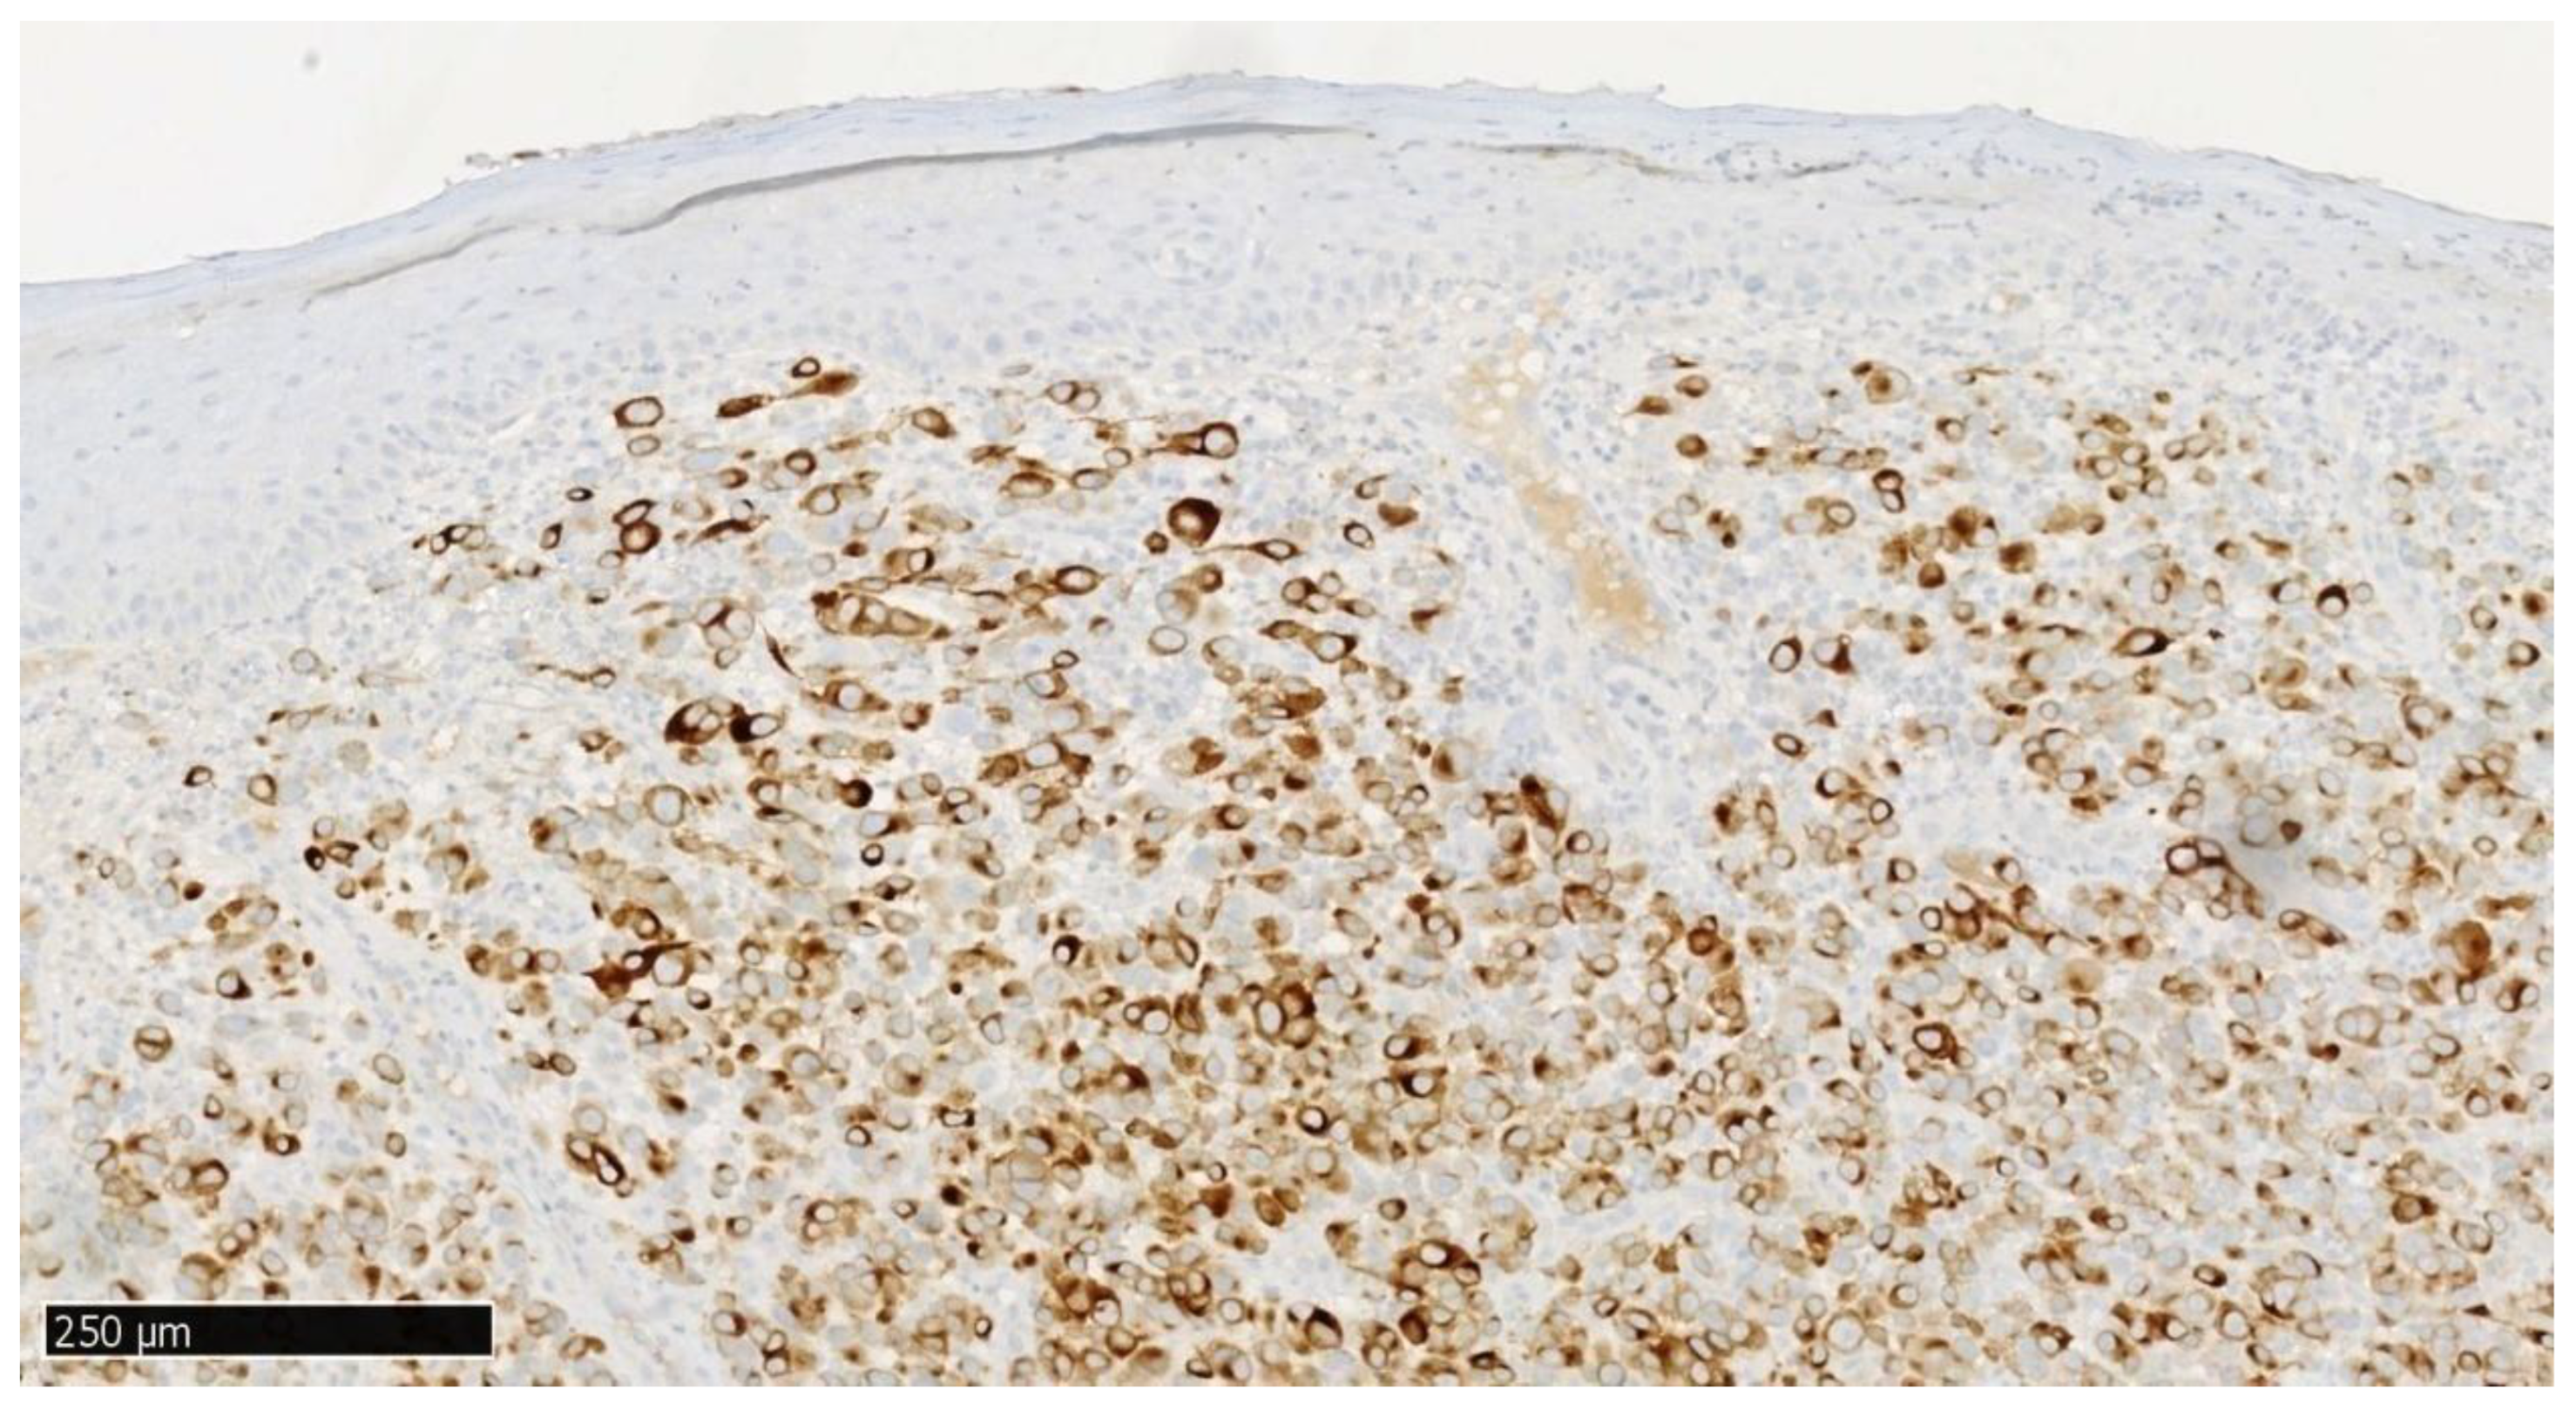

Immunohistochemistry: S100+, SOX10+, MelanA+, Ki67 high (80% positive in maxilla specimen, 70% positive in mandibular specimen); CK Pan−, LCA−.

S100 and SOX10 staining demonstrated strong positivity in melanoma cells with negative reaction in adjacent epithelium. MelanA/MART1 also showed cytoplasmic positivity in tumor cells, whereas CKAE1/AE3 staining was negative in melanoma cells but positive in normal epithelium (Figure 6, Figure 7, Figure 8 and Figure 9). BRAF mutation negative (There is no information in medical history if the KIT and RNAS mutation was tested.)

Histologically, amelanotic oral mucosal melanoma consists of spindle cells with numerous mitotic figures and no cytoplasmic melanin pigmentation. These malignant tumor cells are characterized by significant pleomorphism, with large, irregular, hyperchromatic nuclei and prominent nucleoli [18]. The cells of malignant oral mucosal melanoma can be visualized using hematoxylin and eosin staining. However, if melanin is absent in amelanotic melanoma, immunohistochemical (IHC) staining should be performed to obtain additional diagnostic information. CK and LCA staining are used for differential diagnosis with squamous cell carcinoma and lymphoma. The IHC panel in our case (SOX10/S100 positive; CK Pan negative; variable melanocytic marker expression) aligns with recommended diagnostic strategies for OMM. Specifically, SOX10 has demonstrated greater expression stability compared to S100 in melanoma diagnostics, while Melan-A may be negative in amelanotic variants, highlighting the need for panel-based interpretation rather than reliance on individual markers [17,32]. Moreover, a very high Ki-67 index (70–80% in our case) and elevated mitotic index (MI: upper gum tumor—14/mm2; lower tumor—5/mm2) correspond with more aggressive tumor biology and poorer prognosis in head and neck OMM. High Ki-67 proliferation indices (60–100%) have been correlated with shorter overall survival in mucosal melanoma patients [33,34].

Figure 6. Immunohistochemical staining S100, final magnification ×100, specimen from the upper gingival tumor. Scale bar: 250 μm.